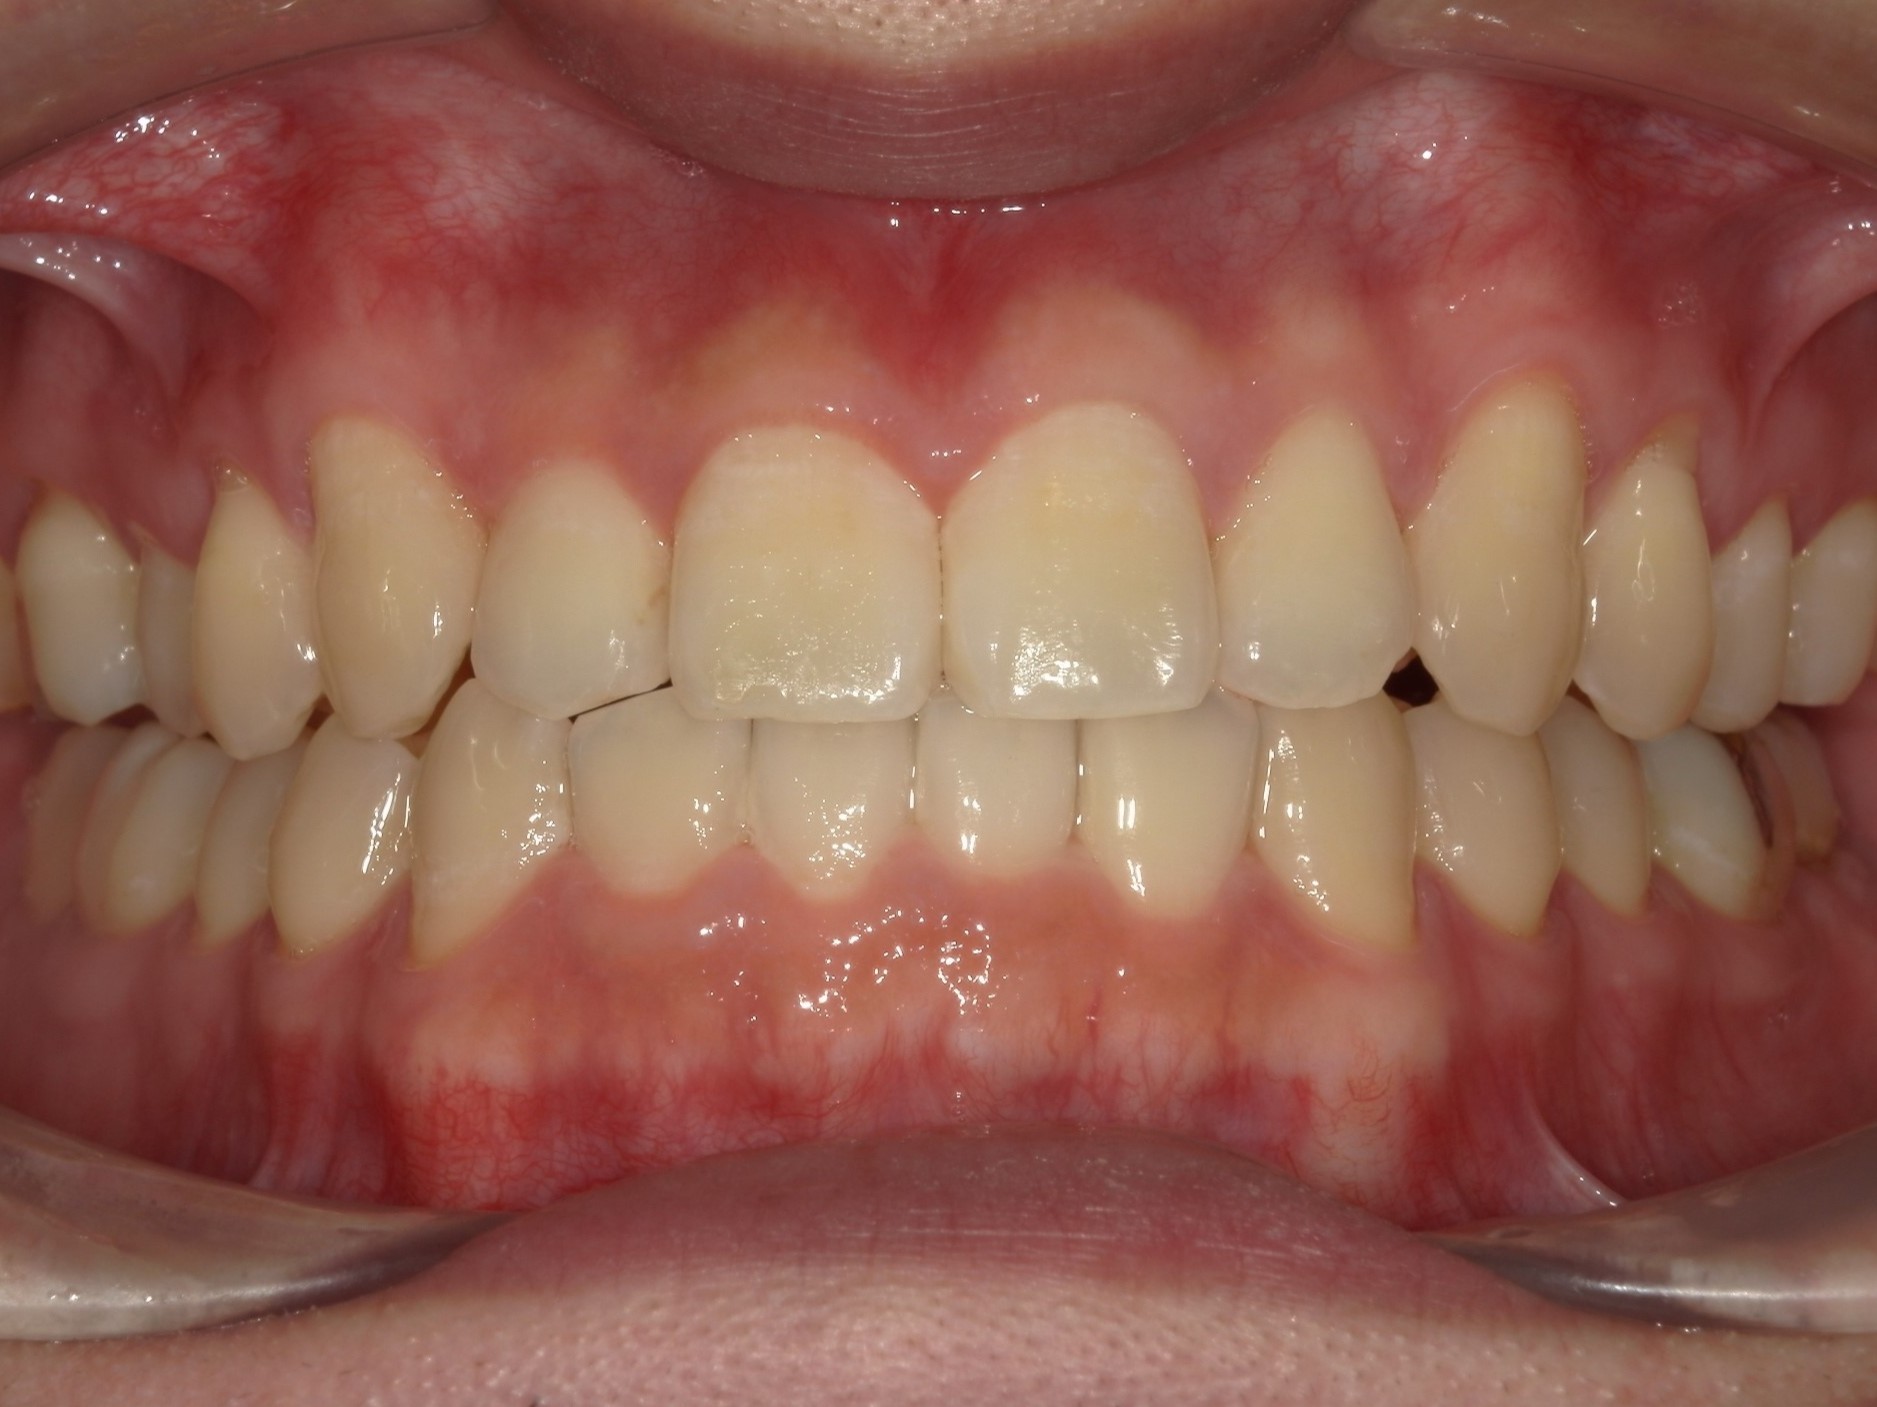

20代男性の方で、叢生・全体的な歯並び(不揃い・ガタガタ・不正咬合)が気になる患者様です。

歯が重なり合う状態は、見た目の問題だけではなく歯磨きが難しくなり虫歯や歯周病を引き起こすリスクにもなるため、インビザライン(重程度)矯正を行いました。

治療期間は約1年半、枚数は89枚です。

治療前

治療内容 歯が重なり合う状態は、見た目の問題だけではなく歯磨きが難しくなり虫歯や歯周病を引き起こすリスクにもなるため、インビザライン(重程度)矯正を行いました。

左右の下顎智歯(親知らず)抜歯をしました。